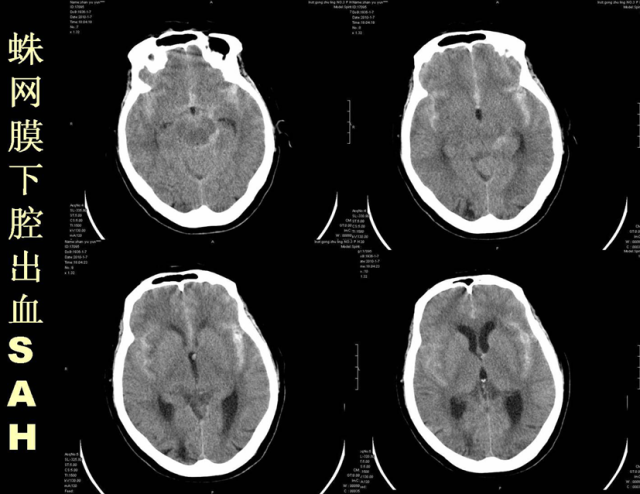

急性颅脑损伤篇

03